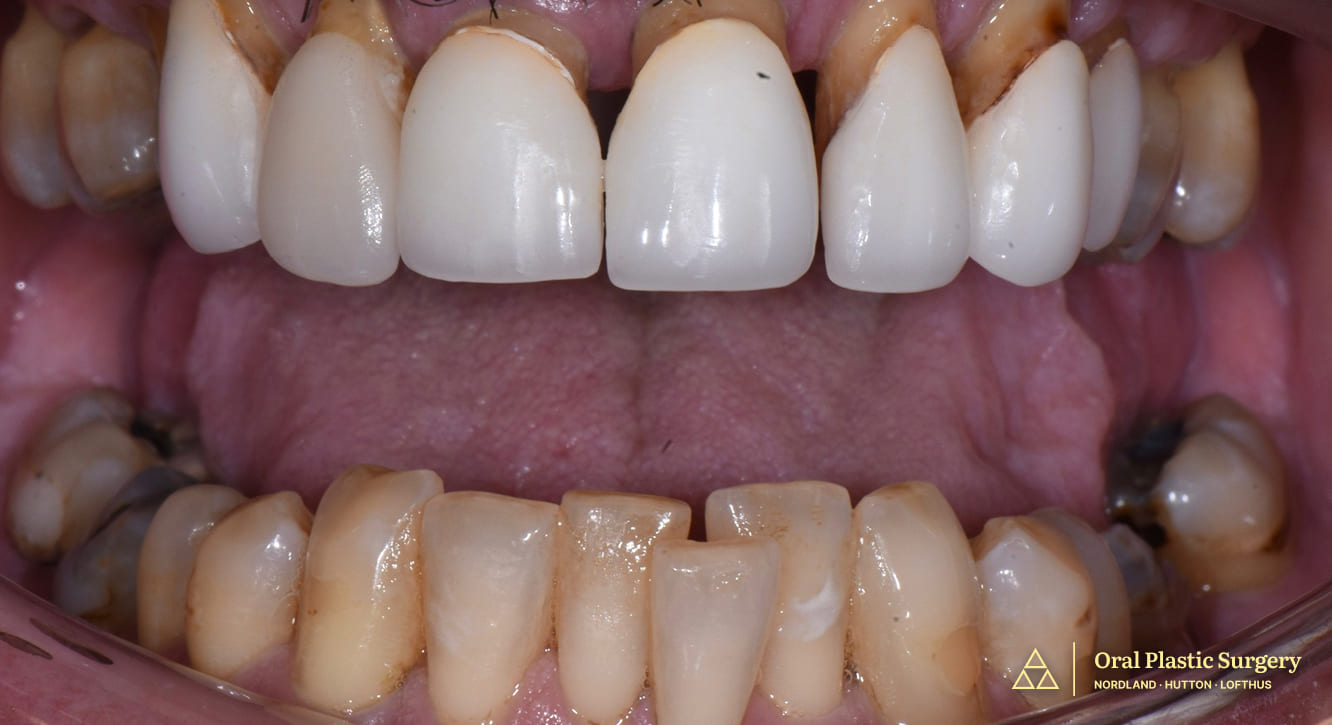

Initial presentation showing exposed, worn, and discolored root surfaces with chipping and discoloration of maxillary anterior teeth.

Post connective tissue grafting showing dramatic improvement in root coverage, tissue color, and gingival contour prior to final restorative work.